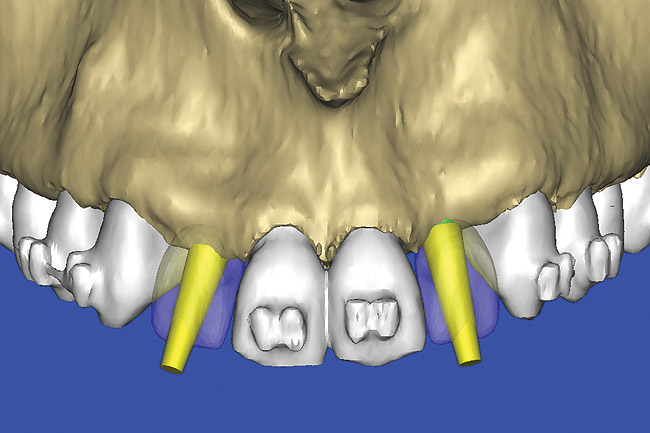

Figure 13  SOFTWARE IMAGING This allowed for evaluation of virtual implant placement to ensure the facial cortical plate was not perforated.

Figure 13

After the basic plan had been established, it was re-evaluated using interactive 3D images. The reconstructed 3D view of the maxilla clearly illustrated the extent of the bilateral facial concavities, and the root eminences of the adjacent and posterior teeth (Figure 12). The placement of the virtual implants then was evaluated to ensure that the facial cortical plate was not perforated (Figure 13). The implants were labeled individually as “7” and “10,” with the simulated yellow abutment projection indicating the facial-lingual inclination through the bone to the level above the incisal edge of adjacent teeth. The ability to gain a better understanding of these individual root forms cannot be underestimated. The dental literature has suggested certain parameters for placing implants near teeth and implants next to other implants. However, there is little scientific 3D documentation to support these suggested rules.5-10 The use of an interactive treatment-planning software application permits closer scrutiny of previously difficult-to-visualize areas, and can now be used to redefine perceptions of spatial positioning of implants, especially when in close proximity to natural tooth roots, vital anatomy, and adjacent implants.27-29

Using different masking (segmentation) and threshold Hounsfield unit values, several new 3D bone volumes can be created which offer invaluable information. To help determine the final position of each implant a new bone model was created with a Hounsfield unit value of 1480, which eliminated all but the densest objects included in the scan data. (Results may vary depending on the CBCT machine used.) The inner and outer layers of bone were removed, leaving the underlying enamel and root structure of the teeth (Figure 14). After the bone had been stripped away, the root inclinations were examined closely. The most striking findings confirmed the rotated position of the right central, while revealing the slight mesial dilaceration of the root apex, which converged on the space needed for the path of the potential implant (Figure 15). The schematic shapes of the proposed implants were visualized for the right and left lateral spaces in different rotations of the 3D maxillary arch. It was at this point that a determination was made as to the appropriate implant shape and type that would fit the available space while avoiding encroachment on adjacent tooth roots. A tapered design implant (Tapered Screw-Vent®, Zimmer Dental, www.zimmerdental.com) was chosen from the large virtual library. With the SIMPlant software, the virtual library contains data from dozens of implant manufacturers and realistic computer-aided design representations as seen in Figure 16 through the translucent bone. The position of the left implant can be visualized with adequate mesial-distal distance between adjacent tooth roots (Figure 17) and a more delicate placement (Figure 18).